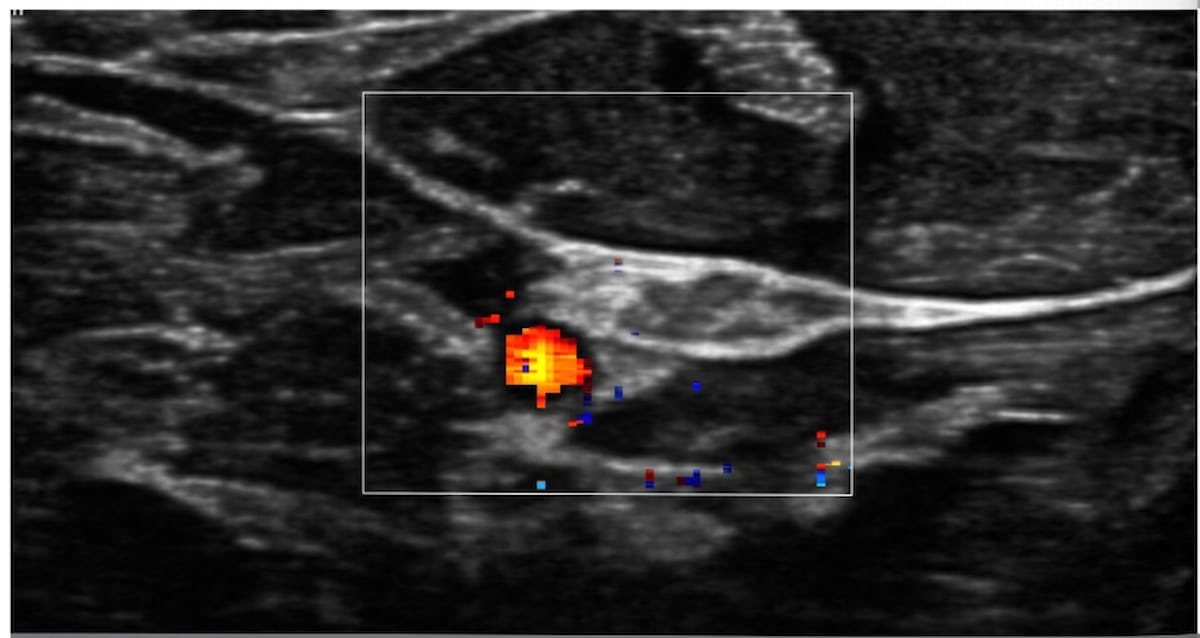

Diagnostic Ultrasound expects sales to double this year, aidedby Bard's investment, the Bard marketing agreement, an equivalentinvestment by another unnamed source, and expanded internationalbusiness. The company's other product is Versadopp 10, a pen-sizedDoppler blood-flow sensor used to evaluate the risk of strokeor peripheral artery disease and to assist in surgery.